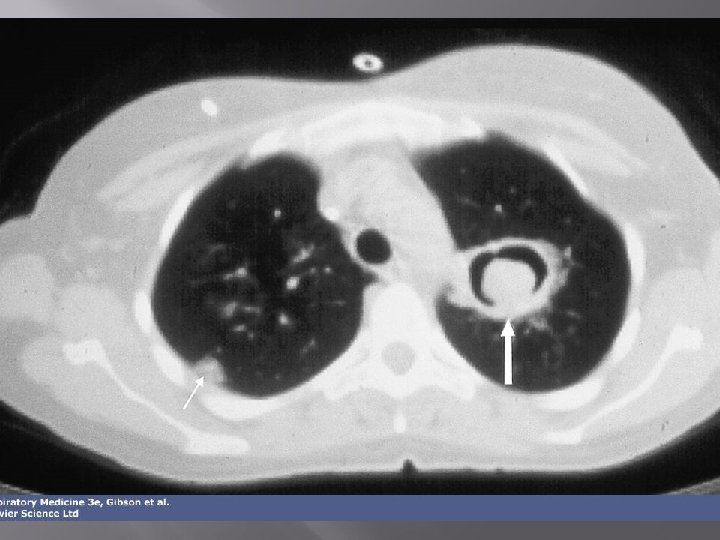

„Halo sign” 14